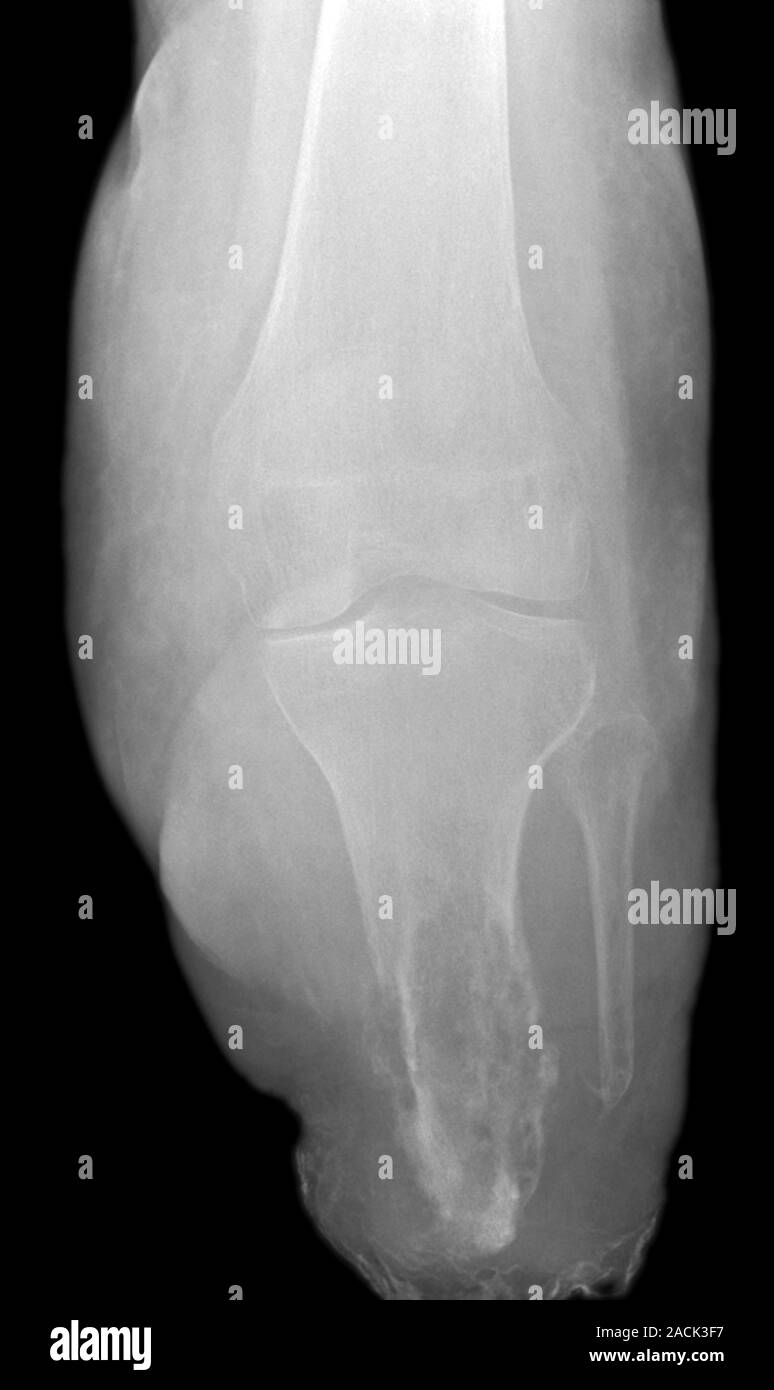

From www.alamy.com

Bone infection. Xray of the knee of a 75 year old female patient with Arm Bone Infection In adults, osteomyelitis can be either acute or chronic. A bone biopsy will reveal what type of germ is causing your infection so your doctor can choose an antibiotic that works well. Osteomyelitis may occur as a result of a bacterial bloodstream infection, sometimes called bacteremia, or sepsis, that spreads to the bone. People with diabetes, hiv, or. It can. Arm Bone Infection.